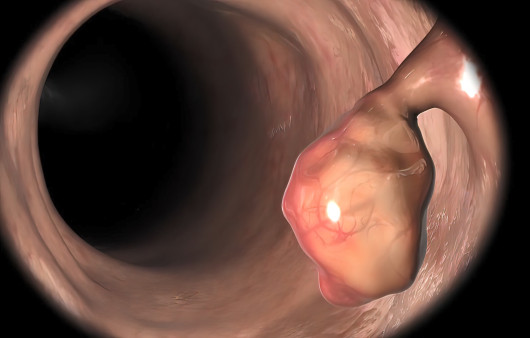

일반적으로 식도암은 식도 점막층에서 거의 독점적으로 발생하지만, 의학적으로 식도암은 자궁경부 식도암, 흉부 식도암, 위식도 접합부암 등으로 세분화되며, 식도암 세포의 종류에 따라 편평세포암, 선암, 육종, 림프종, 흑색종 등으로도 나뉩니다.

암이 진행됨에 따라 내강이 좁아져 처음에는 고기와 같은 음식부터 나중에는 물이나 죽까지 삼키기 어려워질 수 있습니다. 또한 한입 크게 먹을 때 무언가 걸리는 듯한 느낌이 들거나 가슴과 등에 무언가 걸리거나 아픈 느낌이 들 수도 있습니다.

식도암의 치료는 초기에 발견하는 시기에 따라 많이 달라지는데, 조절이 가능한 경우 내시경 조절 수술을 통해 식도암을 제거하며, 초기인 경우 식도절제술이 평균적으로 표준 식도암 치료법입니다.